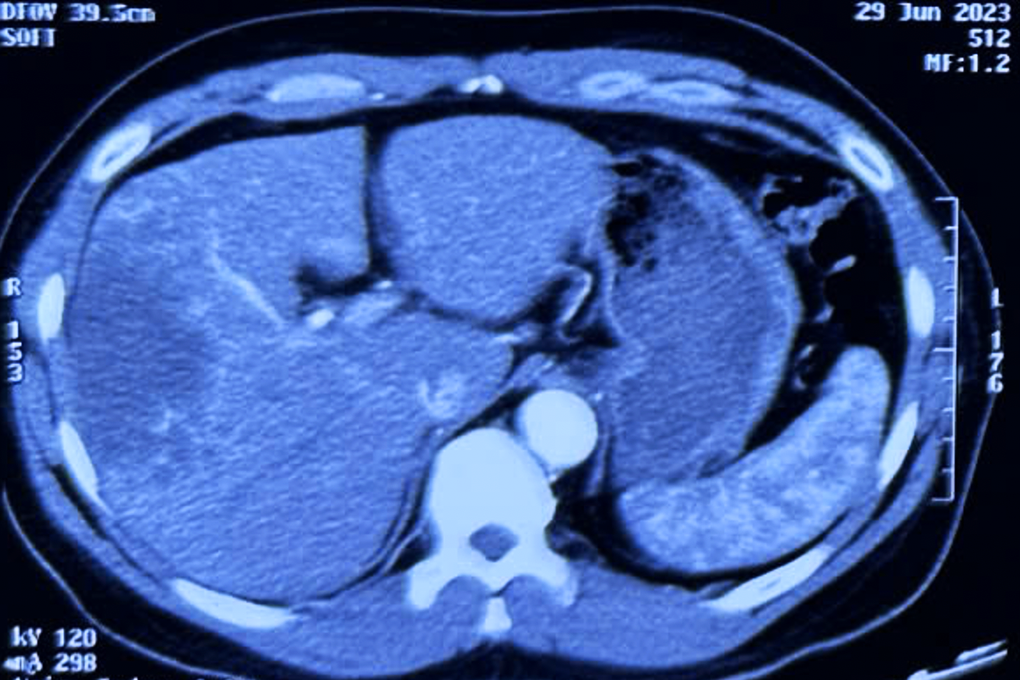

Hình ảnh chụp chiếu của một bệnh nhân mắc ung thư đường mật di căn xa (Ảnh: BS).

Như trường hợp của bệnh nhân N.V.Q. (SN 1974), nhập viện tháng 6/2023 do đau bụng, với tiền căn viêm gan B, nội soi ghi nhận viêm sung huyết dạ dày, trĩ nội. Ảnh chụp CT Scan cho thấy bệnh nhân có tổn thương gan đa ổ 8cm. Kết quả giải phẫu bệnh xác định tình trạng ung thư đường mật, đã di căn đa ổ.